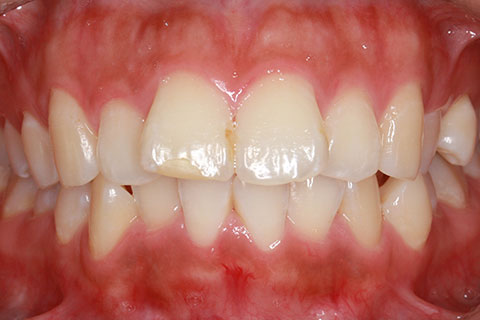

前歯のみの部分的舌側矯正3(矯正期間4ヶ月)

- 年齢・性別

- 33歳

- 治療期間

- 4ヶ月

- 抜歯

- なし

- 治療費

- 50万円

- 備考

- マルチブラケットを用いた矯正治療

- 治療内容

- 非抜歯にてIPRを併用したリンガル矯正治療。

- 施術の副作用(リスク)

- 裏側矯正では装置に慣れるまで発音しづらい場合がある。